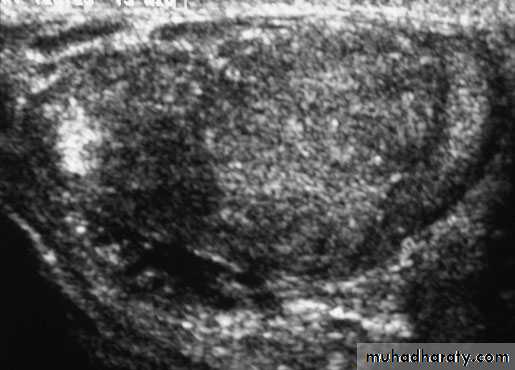

Urinary tract ultrasound scan to diagnose reflux

Scrotal U/S

U/S scanning of the testis